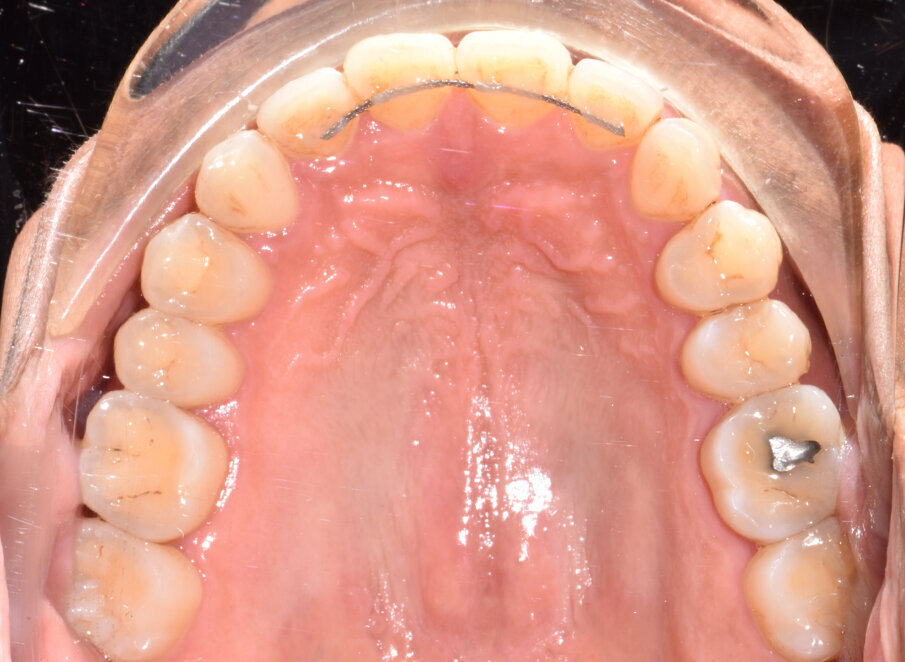

A 56-year-old female patient presented with a Class III malocclusion, anterior crowding and a 2-3 mm anterior open bite. Clinical photographs showed an ideal incisor display upon smiling. The panoramic film was unremarkable, and the lateral cephalometric film revealed a negative 1 mm overjet. (Figs. 1 to 10)

Specifically, the plan prescribed upper arch expansion and bilateral molar and second premolar intrusion of 3 mm. To support intrusion and prevent reciprocal lifting of the aligners, 4 mm wide occlusally beveled retentive attachments were designed and placed on the premolars. (Fig. 11)